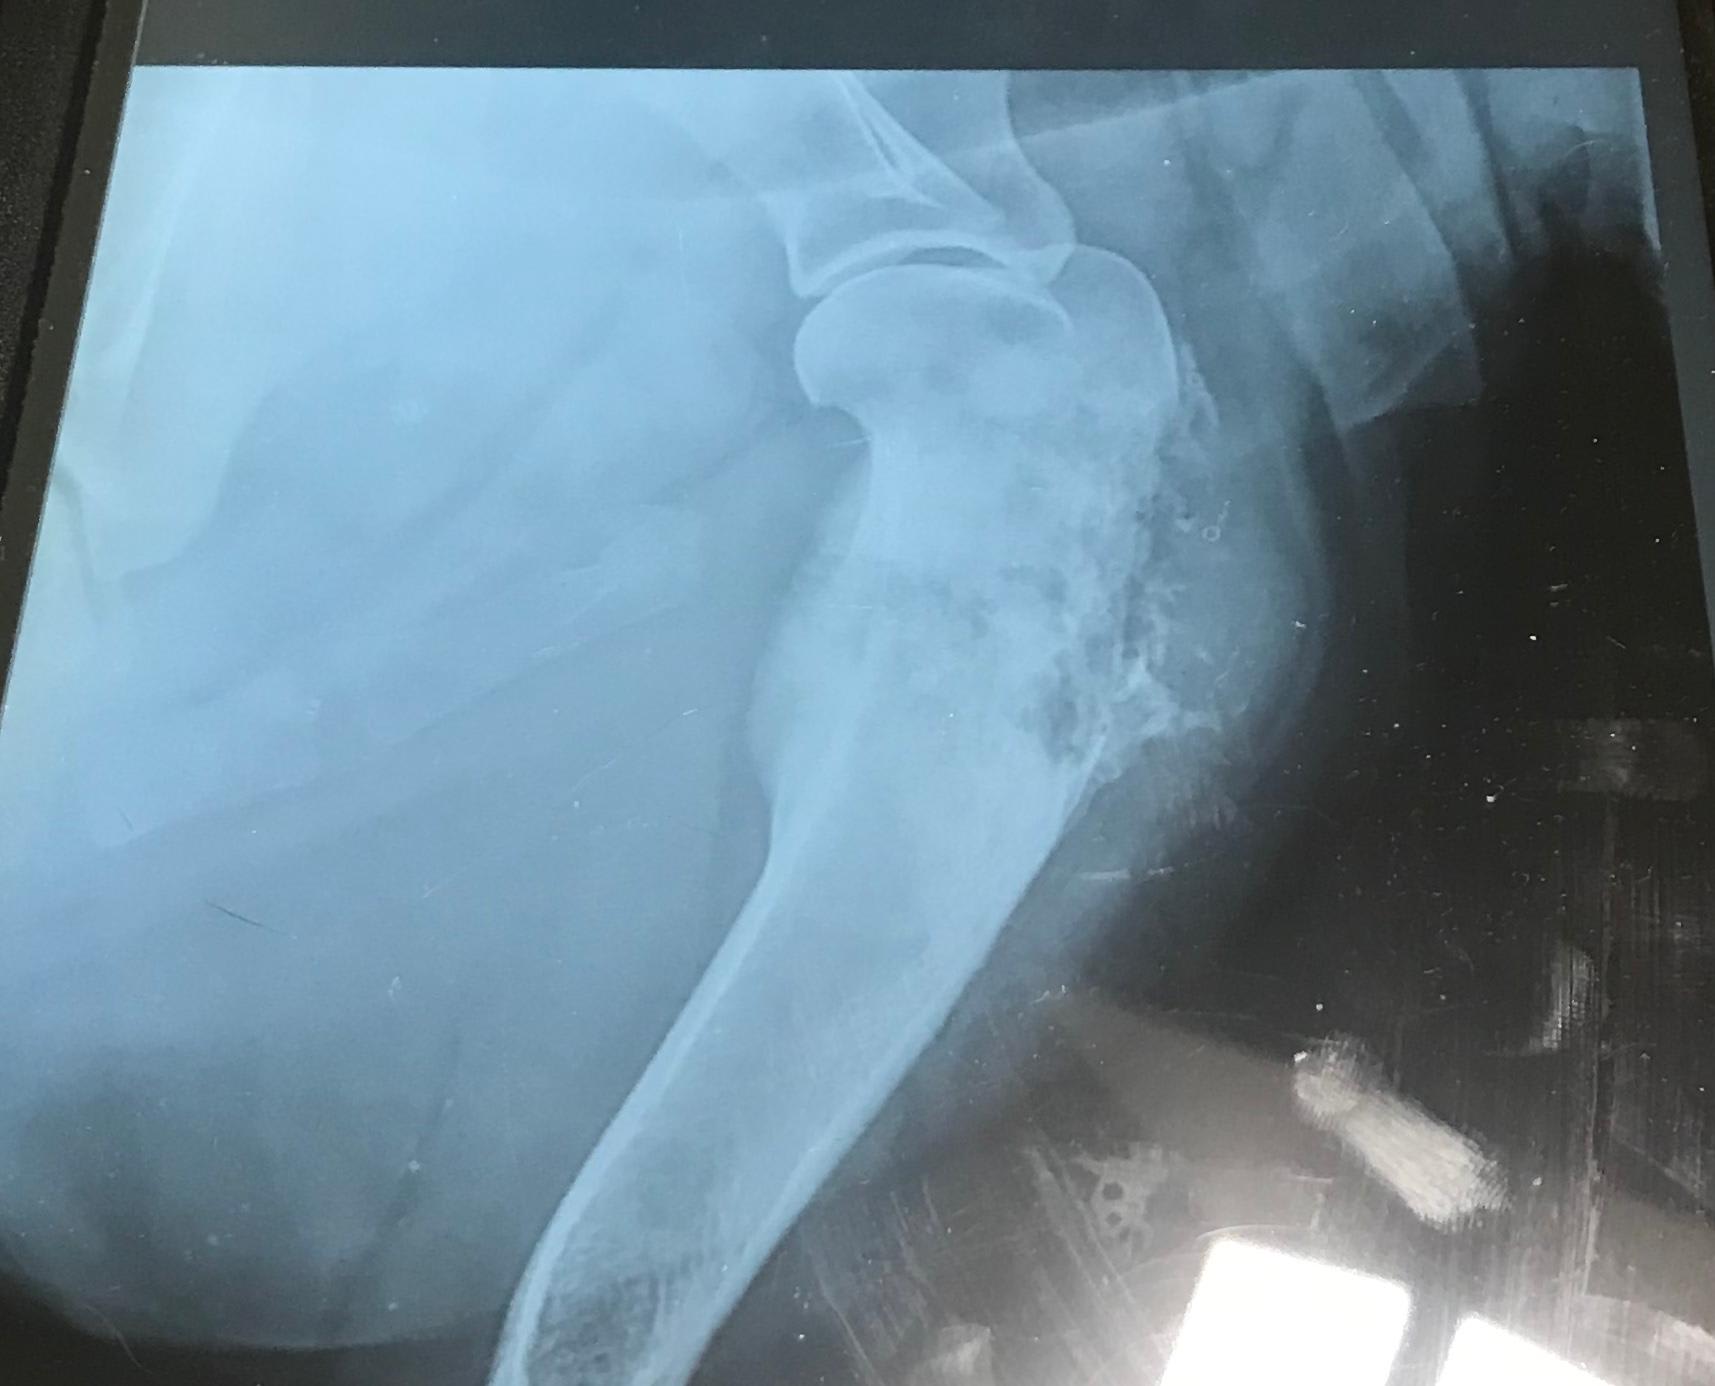

Male neutered 160lbs 3-4years old X-ray of right front leg What is wrong with my dog’s leg?

Hello and thank you for reaching out about your dog. These xrays are very concerning for either a fungal infection (very much dependent on where you are living) or a bone cancer (osteosarcoma). These xrays I am sure have also been evaluated by your veterinarian and hopefully a radiologist as well. I would recommend chest xrays to look for cancer metastasis or diffuse fungal infection and you may need to have your veterinarian perform a bone core biopsy for a diagnosis. This is usually very painful and your dog should be on good pain meds and rest during this time. Treatment options are very different for bone cancer vs. fungal infection so a proper diagnosis is extremely important. Best of luck!